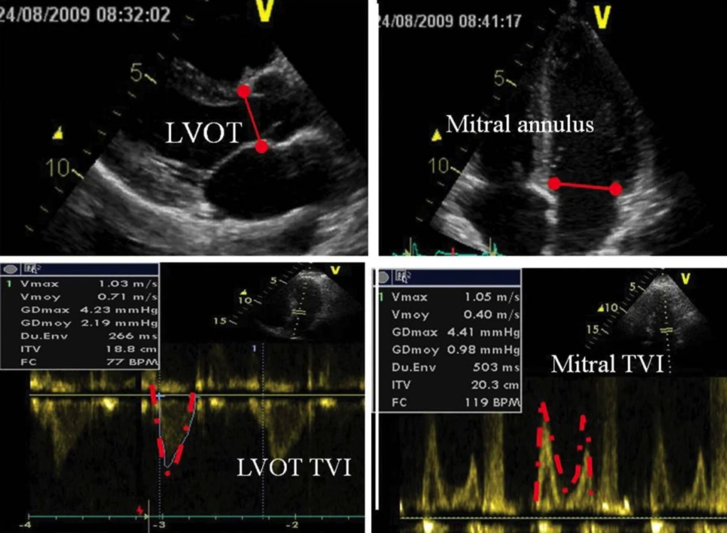

- Doppler PW and CW

- PW Doppler

- locate the site of peak velocity

定位峰值速度的位置

- CW Doppler

- Peak velocity/VTI

峰值速度 / 速度时间积分 - Mean gradient

平均压差 - Peak gradient (4V2)

峰值压差

- 3-5 cycles to adjust for respiratory changes

3-5 个周期以适应呼吸变化

# Pulmonary Regurgitation (PR)

- Diastolic jet in the RVOT 右室流出道中的舒张期血流

- Jet length >10 mm 射流长度 > 10 毫米

- Physiological vs pathological PR: duration of flow ie holodiastolic

生理与病理 PR: 血流持续时间,即全舒张期 - Jet width: wider jets worse; evaluate at jet origin "vena contracta" [2]

射流宽度:较宽的射流更糟;在反流起始处评估缩流颈宽度 - Severe PR: jet width vs RVOT width > 55-65%

严重 PR: 射流宽度 vs RVOT 宽度 > 55-65% - Detection of flow reversal in pulmonary arteries

肺动脉血流逆转的检测

PV VTI / LVOT VTI7 肺瓣 VTI 与左室流出道 VTI 之比

| Slightly increased | Intermediate | Greatly increased |

- PW Doppler: $$ \text{difference between reverse and forward VTI} = \% \text{regurgitant flow} $$

PW 多普勒:反向与正向 VTI 的差值 = 反流血流的百分比- PV forward VTI vs AV forward VTI < 1 normally